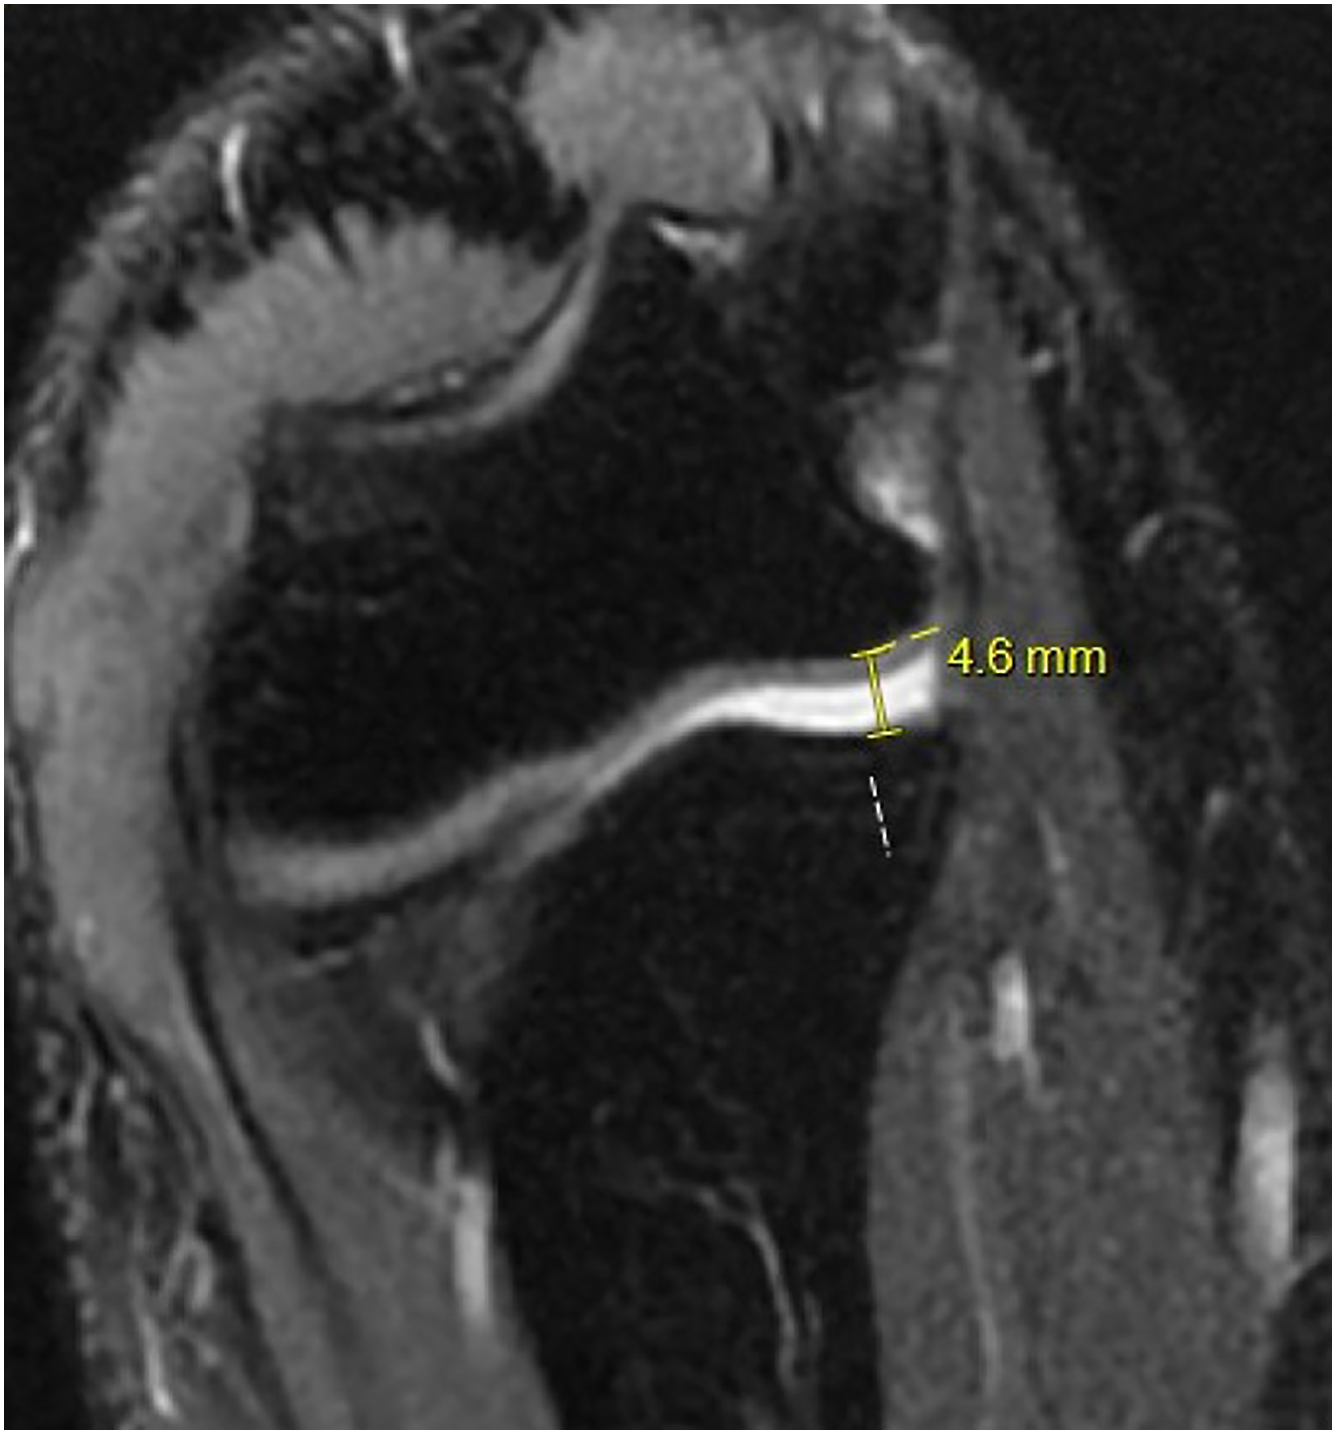

Conventional 3 Tesla (3T) MRI and MR Arthrograms (MRA) are the study of choice for diagnosing UCL injuries. MRA has slightly better diagnostic accuracy than conventional 3T MRI. MRA is 100% sensitive and specific and 3T MRI is 100% sensitive and 89% specific for detecting full-thickness UCL tears. The improved diagnostic capabilities should be weighed against the invasiveness, added patient discomfort, and increased cost. A flexed elbow valgus external rotation (FEVER) MRI view was recently described as a dynamic assessment of the competency of the UCL that may improve diagnostic accuracy. A FEVER view is obtained using a 30° coronal oblique MRI view to be parallel with the long axis of the UCL while placing the elbow at 90° with valgus stress applied and subsequent measurement of the ulnohumeral gapping from the subchondral edges ( Fig. 3 ); computed tomography scan is reserved for surgical planning, particularly revision cases to assess the amount of tunnel widening or bone loss, as well as for large posteromedial osteophytes.